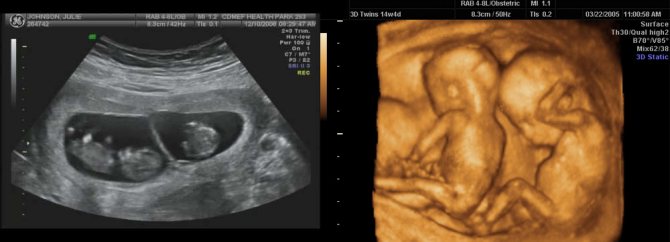

Как выглядит двойня на ранних сроках? Поначалу врач видит только два темных пятнышка. Кроме того, отчетливо прослушивается биение двух сердец, видны две плаценты и два амниотических пузыря. На фото можно увидеть снимок УЗИ близнецов.

На ранних сроках при проведении УЗИ оцениваются следующие параметры плода:

Нередко на снимке УЗИ заметно, что один эмбрион меньше другого. Если расхождение невелико и составляет всего лишь несколько миллиметров, то беспокоиться не нужно, размеры выровняются или в процессе беременности, или после рождения малышей.

Ультразвук

Наиболее надежный метод выявления многоплодной беременности – ультразвуковое обследование. Но его проведение на ранних сроках может показать только одного ребенка. В первом триместе вероятность выявления развития многоплодности достигает 29%, во втором и третьем -96%. Иногда происходят невероятные случаи обнаружения при родоразрешении третьего ребенка, не зафиксированного при скринингах.

Если будущая мама ждет троих или даже четверых малышей, бывает так, что двойню врач распознает еще на первом ультразвуке 5-6-й недель, а следующего ребенка – только на плановом сканировании.